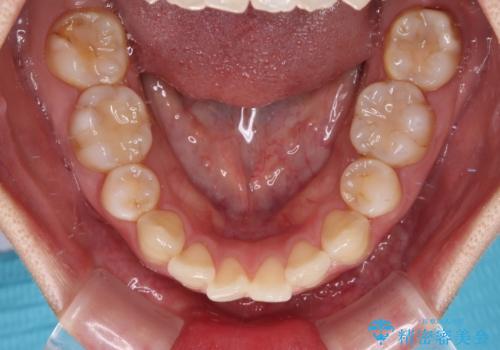

- 上下前歯の後戻りを気にして来院された患者様です。

インビザラインでの治療を希望されていて、デコボコの程度が中等度であり、安価なパッケージにて対応可能と判断されたため、インビザライン・モデレートを用いて矯正治療を行うこととしました。